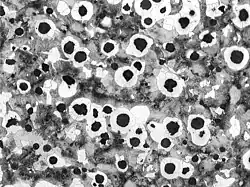

Numerical simulations, like the Finite Element Method and lab techniques, like metallography for materials science, are part of the curriculum of the Engineer Arts et Métiers.